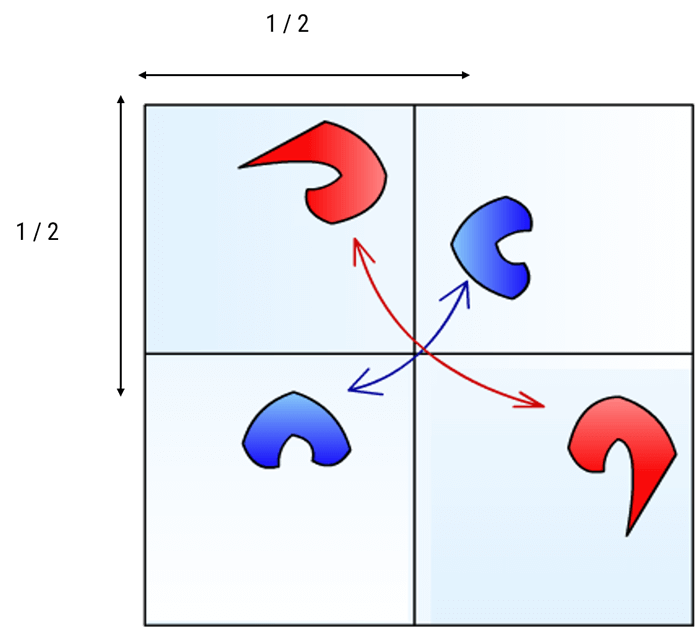

The symmetry of the K Space

The space of Fourier is divided into 4 symmetrical parts, 2 by 2.The K space is symmetrical according to a complex conjugated symmetry around the center. This property is used for rapid sequences for which we fill in only half the Fourier space and the other half is mathematically deduced. This is the case for single-shot fast spin echoes known as SSFSE or Haste sequences. Haste stands for “half acquisition spin turbo echo.

Center and Periphery of the K Space

One of the most important properties of the Fourier space is that the center contains information on contrast and the periphery contains information on spatial resolution. This notion is indispensable for understanding the notion of effective TE and for understanding how filling the Fourier space differently can be used to create specific vascular sequences.

Contrast and Resolution

To summarize, the center of the K space codes for the contrast resolution. Whereas, the periphery of the K space codes for the spatial resolution.